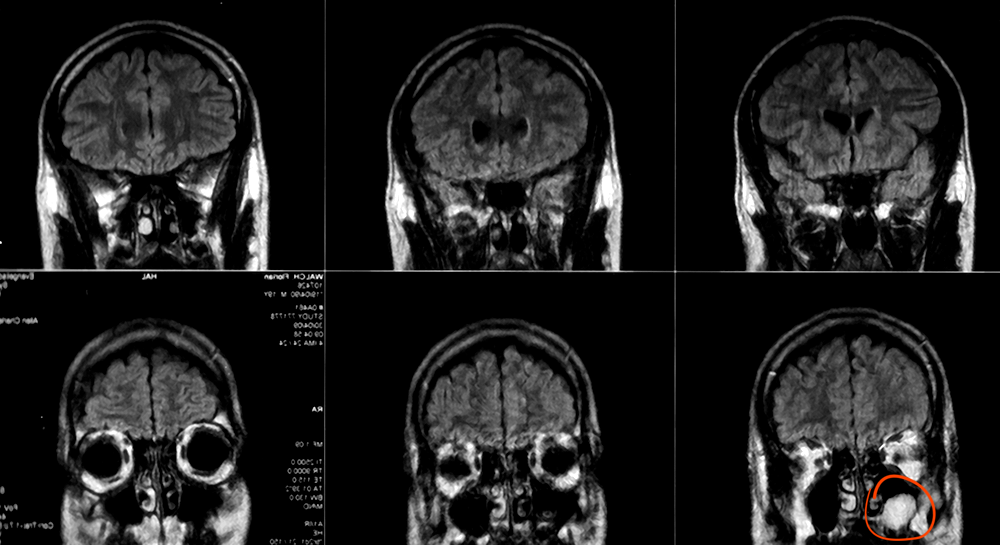

Lower right one, the big white thing that fucks up the beautiful symmetry of my sinuses: